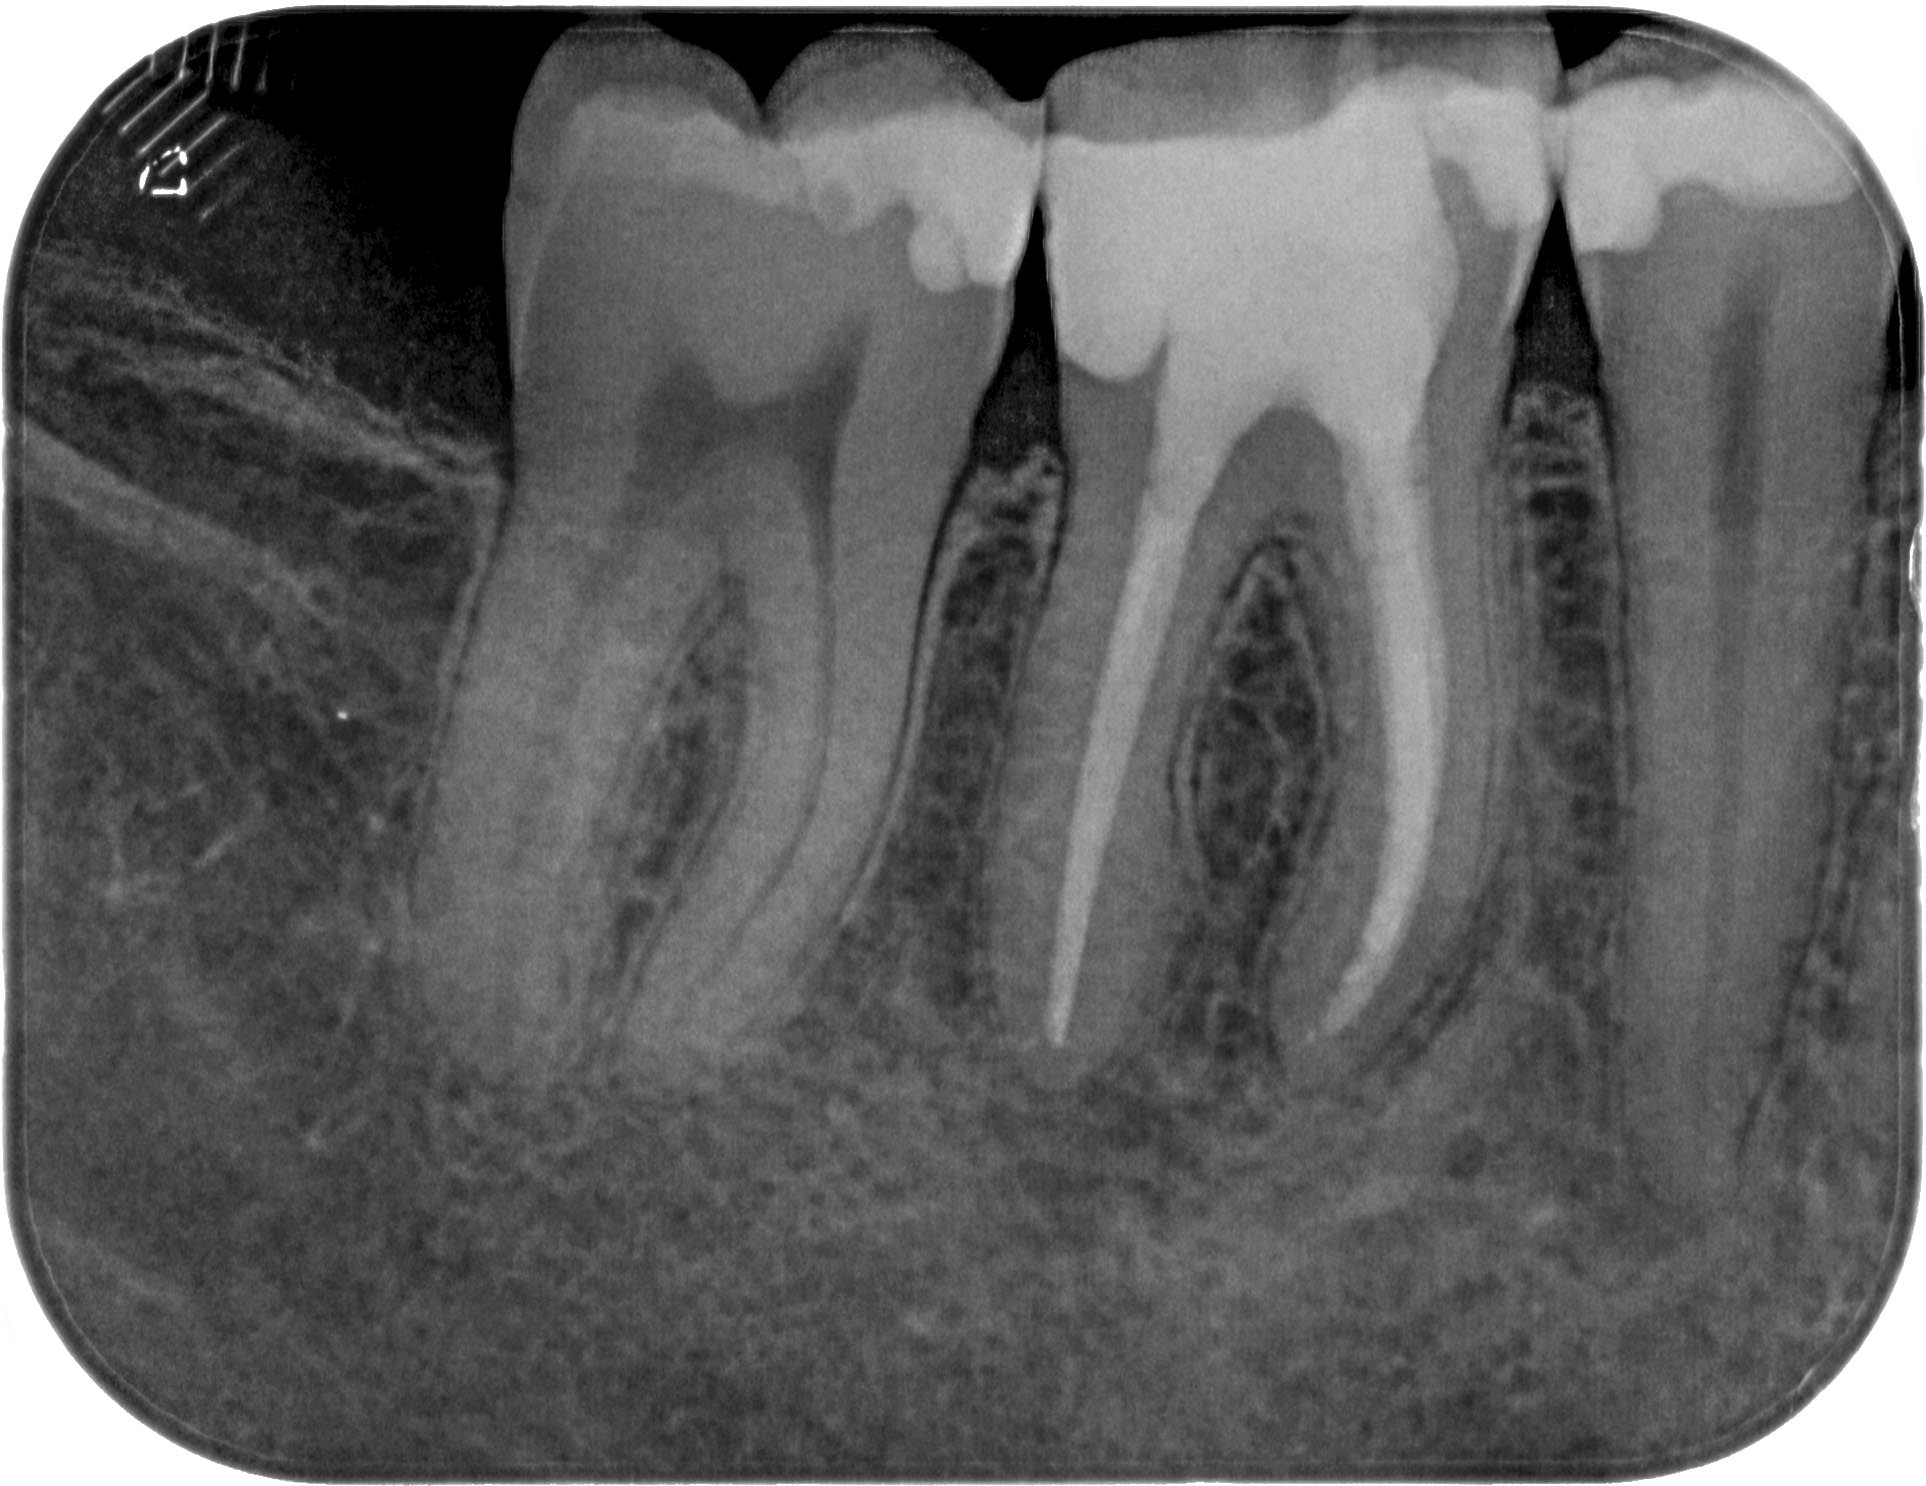

WS46 (4 von 4) Veröffentlicht 21. März 2016 am 1926 × 1486 in Calciumhydroxid- Überpressung (2) 21. März 2016